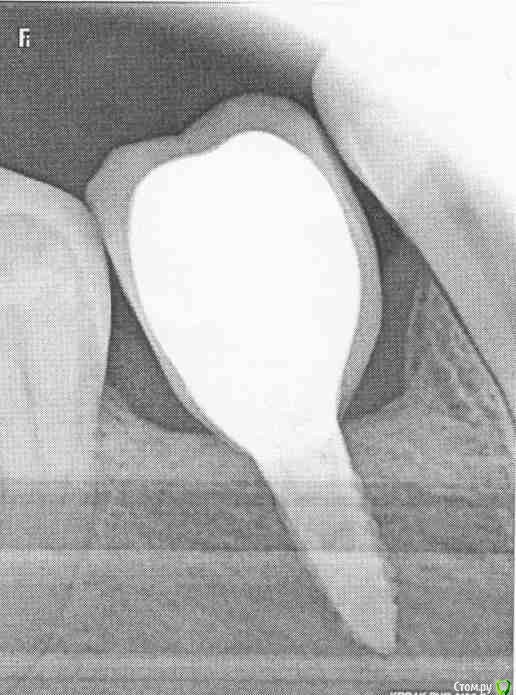

dok1 Опубликовано 16 февраля, 2017 Поделиться Опубликовано 16 февраля, 2017 Выложите снимок импланта. Только чёткий. Ещё лучше срез КТ. Ссылка на комментарий

Alex19_73 Опубликовано 17 февраля, 2017 Автор Поделиться Опубликовано 17 февраля, 2017 К сожалению снимок после имплантации пока не делал, сразу после имплантации врач делал томографию, но она есть наверно только на компьютере в клинике. Перед протезированием имплант был в хорошем (насколько я могу судить) состоянии под нагрузкой проверяли. Был вчера у ортопеда, оказалось что это не цемент а коронка, просто если смотреть спереди низ кажется светлее. Что бы уменьшить застревание еды хирург предложил бесплатно сделать пластику десны, с чем я согласился. Коронку снять не удалось, несмотря на значительные усилия в течении часа . Цемент mis. Пластику решили делать с установленной коронкой. Спасибо ответившим. Ссылка на комментарий